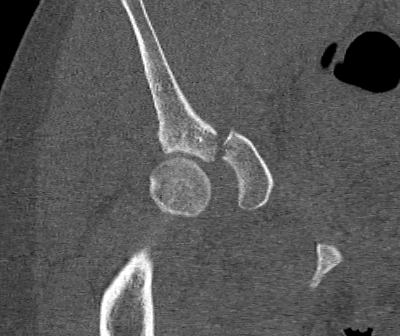

CT

Configuration

1-2 mm sections

CT reconstruction

- remove head to view acetabulum

- beware volume averaging

- used to guide surgery

Diagnose

Loose bodies

Femoral head fractures

Subtle subluxation

Articular steps

Roof arc measurement